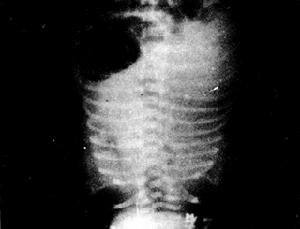

成人呼吸窘迫綜合徵[影像學表現]

1.早期:肺紋理增重模糊,可有小斑片狀陰影,也可無異常X線表現。2.中期:肺內斑片狀或大片狀融合陰影,兩肺外帶比內帶重。3.晚期:兩肺廣泛的片狀陰影,甚至兩肺廣泛實變,心影輪廓消失,僅肋膈角處有少量含氣陰影。此期常合併感染,出現團塊、空洞或膿胸。

4.恢復期;約在發病1周后,病變陰影逐漸消失。5.必須結合病史、臨床表現和血氣分析綜合判斷,氧分壓小於8kPa(60mmHg),一般給氧治療無效,並需除外心源性或非心源性肺水腫。

成人呼吸窘迫綜合徵檢查兩肺有無肺紋理增加、斑片狀陰影或兩肺廣泛密度增加及呈“白肺”外觀。